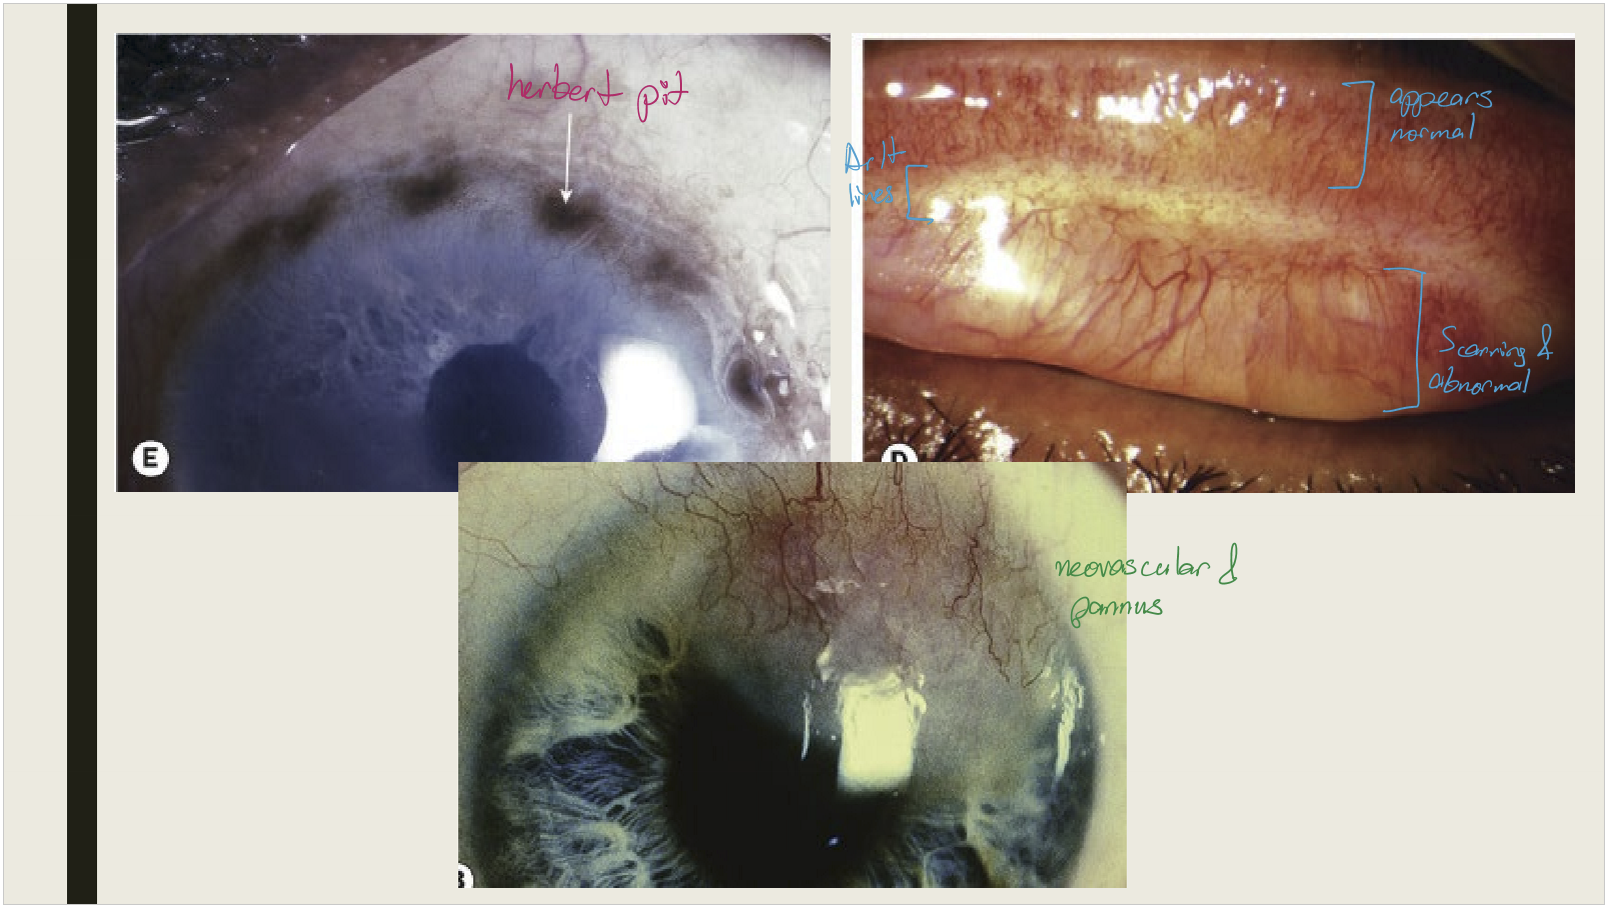

Most commonly affects children between 2–4 years of age. Molluscum lesions are typically seen along the eyelid margin.

<p>Most commonly affects children between 2–4 years of age. Molluscum lesions are typically seen along the eyelid margin.&nbsp;</p>

What are the symptoms and presentations of molluscum contagiosum conjunctivitis?

• Chronic unilateral ocular irritation

• Pale, waxy, umbilicated nodule on the lid margin

• bulbar conjunctival nodule (seen with immunocompromised patients)

• Epithelial keratitis and pannus can be seen in longstanding untreated cases

<ul><li><p>Chronic unilateral ocular irritation&nbsp;</p></li><li><p>Pale, waxy, umbilicated nodule on the lid margin</p></li><li><p>bulbar conjunctival nodule (seen with immunocompromised patients)&nbsp;</p></li><li><p>Epithelial keratitis and pannus can be seen in longstanding untreated cases</p></li></ul><p></p>